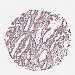

Colorectal cancer

Colon adenocarcinoma